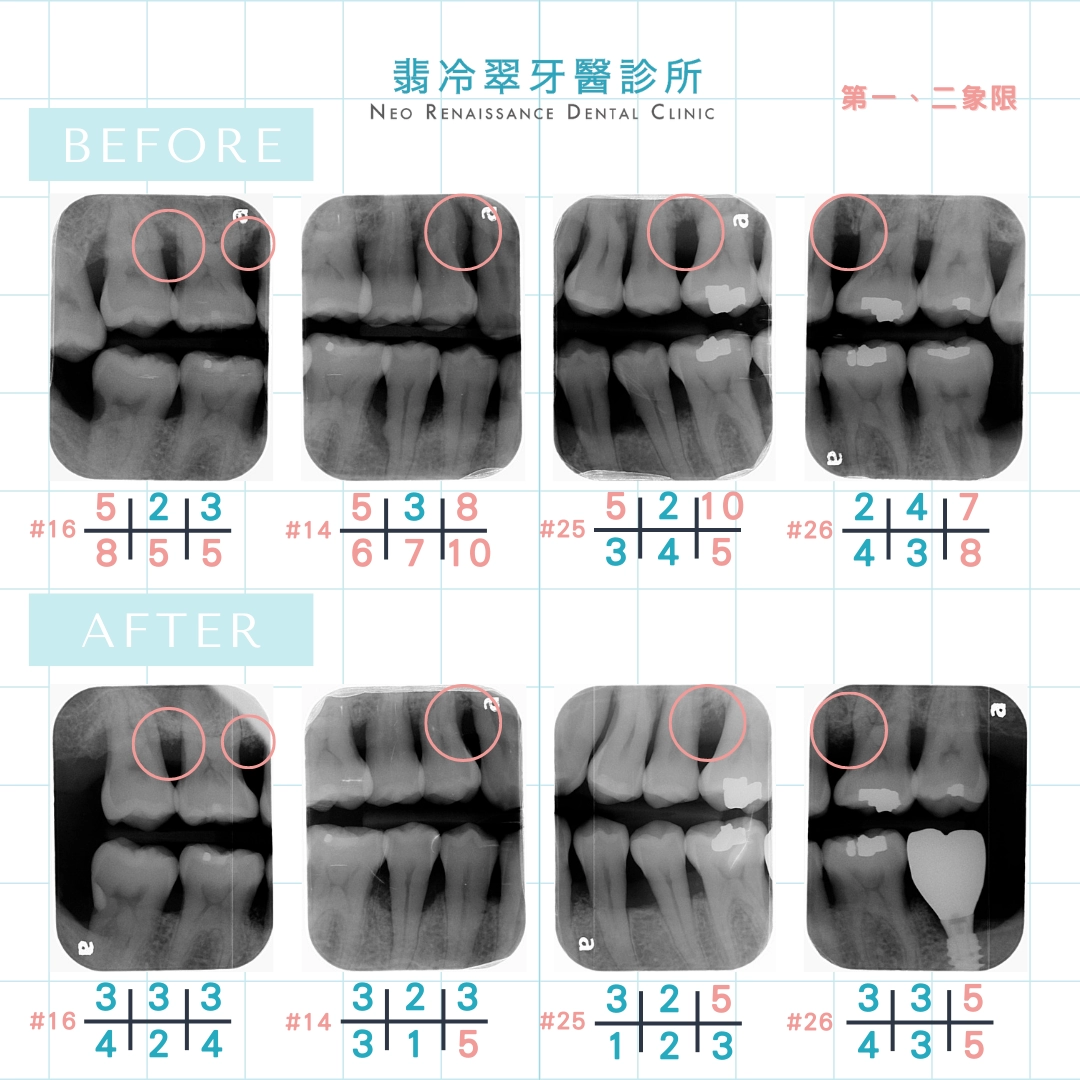

先來說明如何判定有牙周病呢?

醫師會透過有刻度的牙周探針

來測量牙周囊袋的深度

一般健康的牙齦大約在1-3mm以內

超過「5mm以上」就是有牙周病

透過X光片及紅色數字的部分可以發現

原本健康的牙周因牙周病的關係

導致部分的骨頭被侵蝕,而產生很深的囊袋

患者甚至出現牙齒搖晃的狀況!

利用水雷射進行牙周病及補骨的治療

能完整清除死角感染源、有效滅菌、

低疼痛、低出血、傷口小

並有助於刺激健康組織修復,癒合速度加快

另外補骨也像是為骨細胞搭了一座鷹架,

讓原本被吃掉的骨頭漸漸地長回來了

幫助牙床修復再生!